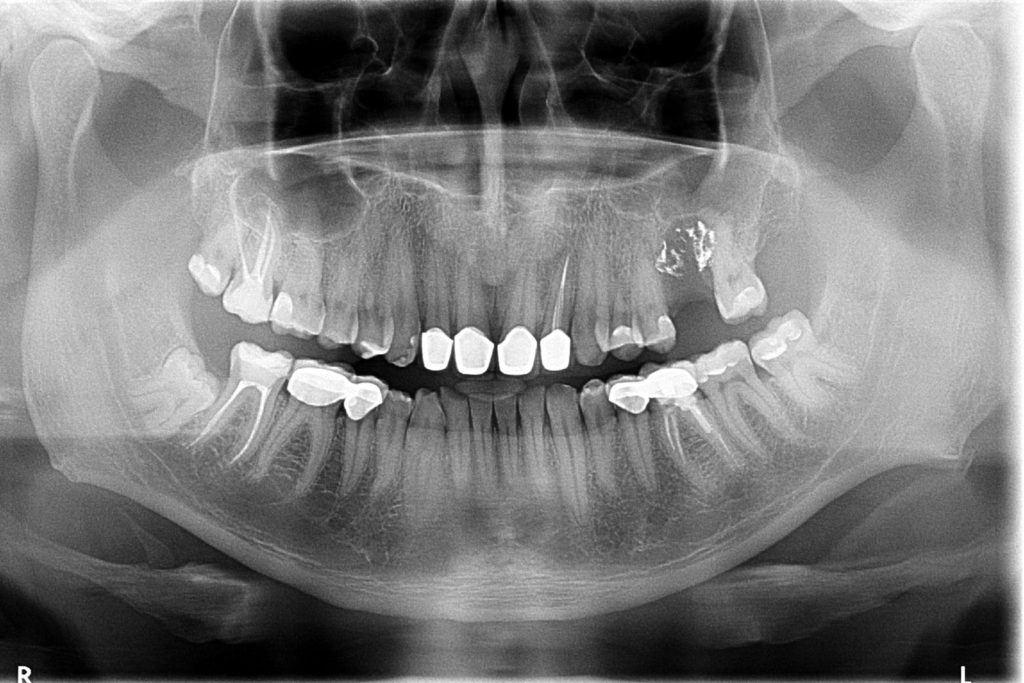

Przed podjęciem leczenia należy określić stopień zaniku kości szczęk oraz żuchwy. W tym celu przeprowadza się badanie kliniczne oraz odpowiednią diagnostykę obrazową pacjenta. Uwzględnia ona zdjęcie panoramiczne OPG jako podstawę dwuwymiarowego obrazowania podłoża kostnego oraz możliwe jest badanie tomograficzne CT lub bardziej precyzyjna tomografia stożkowa CBCT. Opcjonalnie wykorzystywana diagnostycznie tomografia pozwala na bardziej wnikliwą ocenę stopnia zaniku kości w trójwymiarowym, przestrzennym obrazie.

U pacjentów spotykamy 3 typy zaników kości wyrostka zębodołowego szczęk i żuchwy: